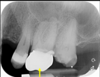

82

is the following periapical pathology or not?

yes

83

yes - root filled - PDL isnt continuous - lamina dura isnt continuous